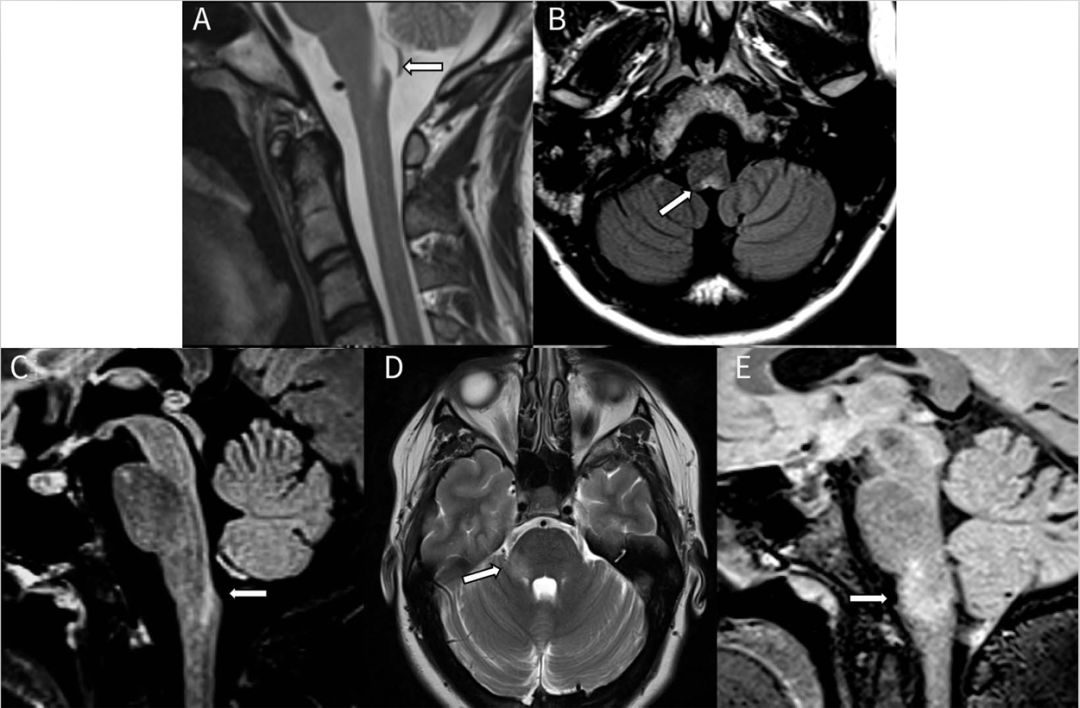

图1多发性硬化症患者的MRI影像。轴位T2加权(A,B)显示脑桥外围界限清楚的卵圆形病灶(箭头)。矢状位FLAIR图像(C,D)显示胼胝体下表面的病灶(C)和垂直于胼胝体的病灶(Dawson指征)(D)。

图2 NMOSD患者的MRI影像。(A-C)顽固性恶心和呕吐(极后区综合征)且血清aquaporporin-4阳性NMOSD患者MRI影像。矢状位T2加权(A)、轴位FLAIR(B)和矢状位FLAIR(C)显示脊髓背侧线性病灶(箭头)。(D-E)髓鞘少突胶质糖蛋白糖蛋白阳性NMOSD患者MRI影像。轴位T2加权(D)和矢状位FLAIR(E)显示在右侧脑桥/小脑中脚以及延髓/桥髓交界处边缘不清的蓬松样病灶(箭头)。